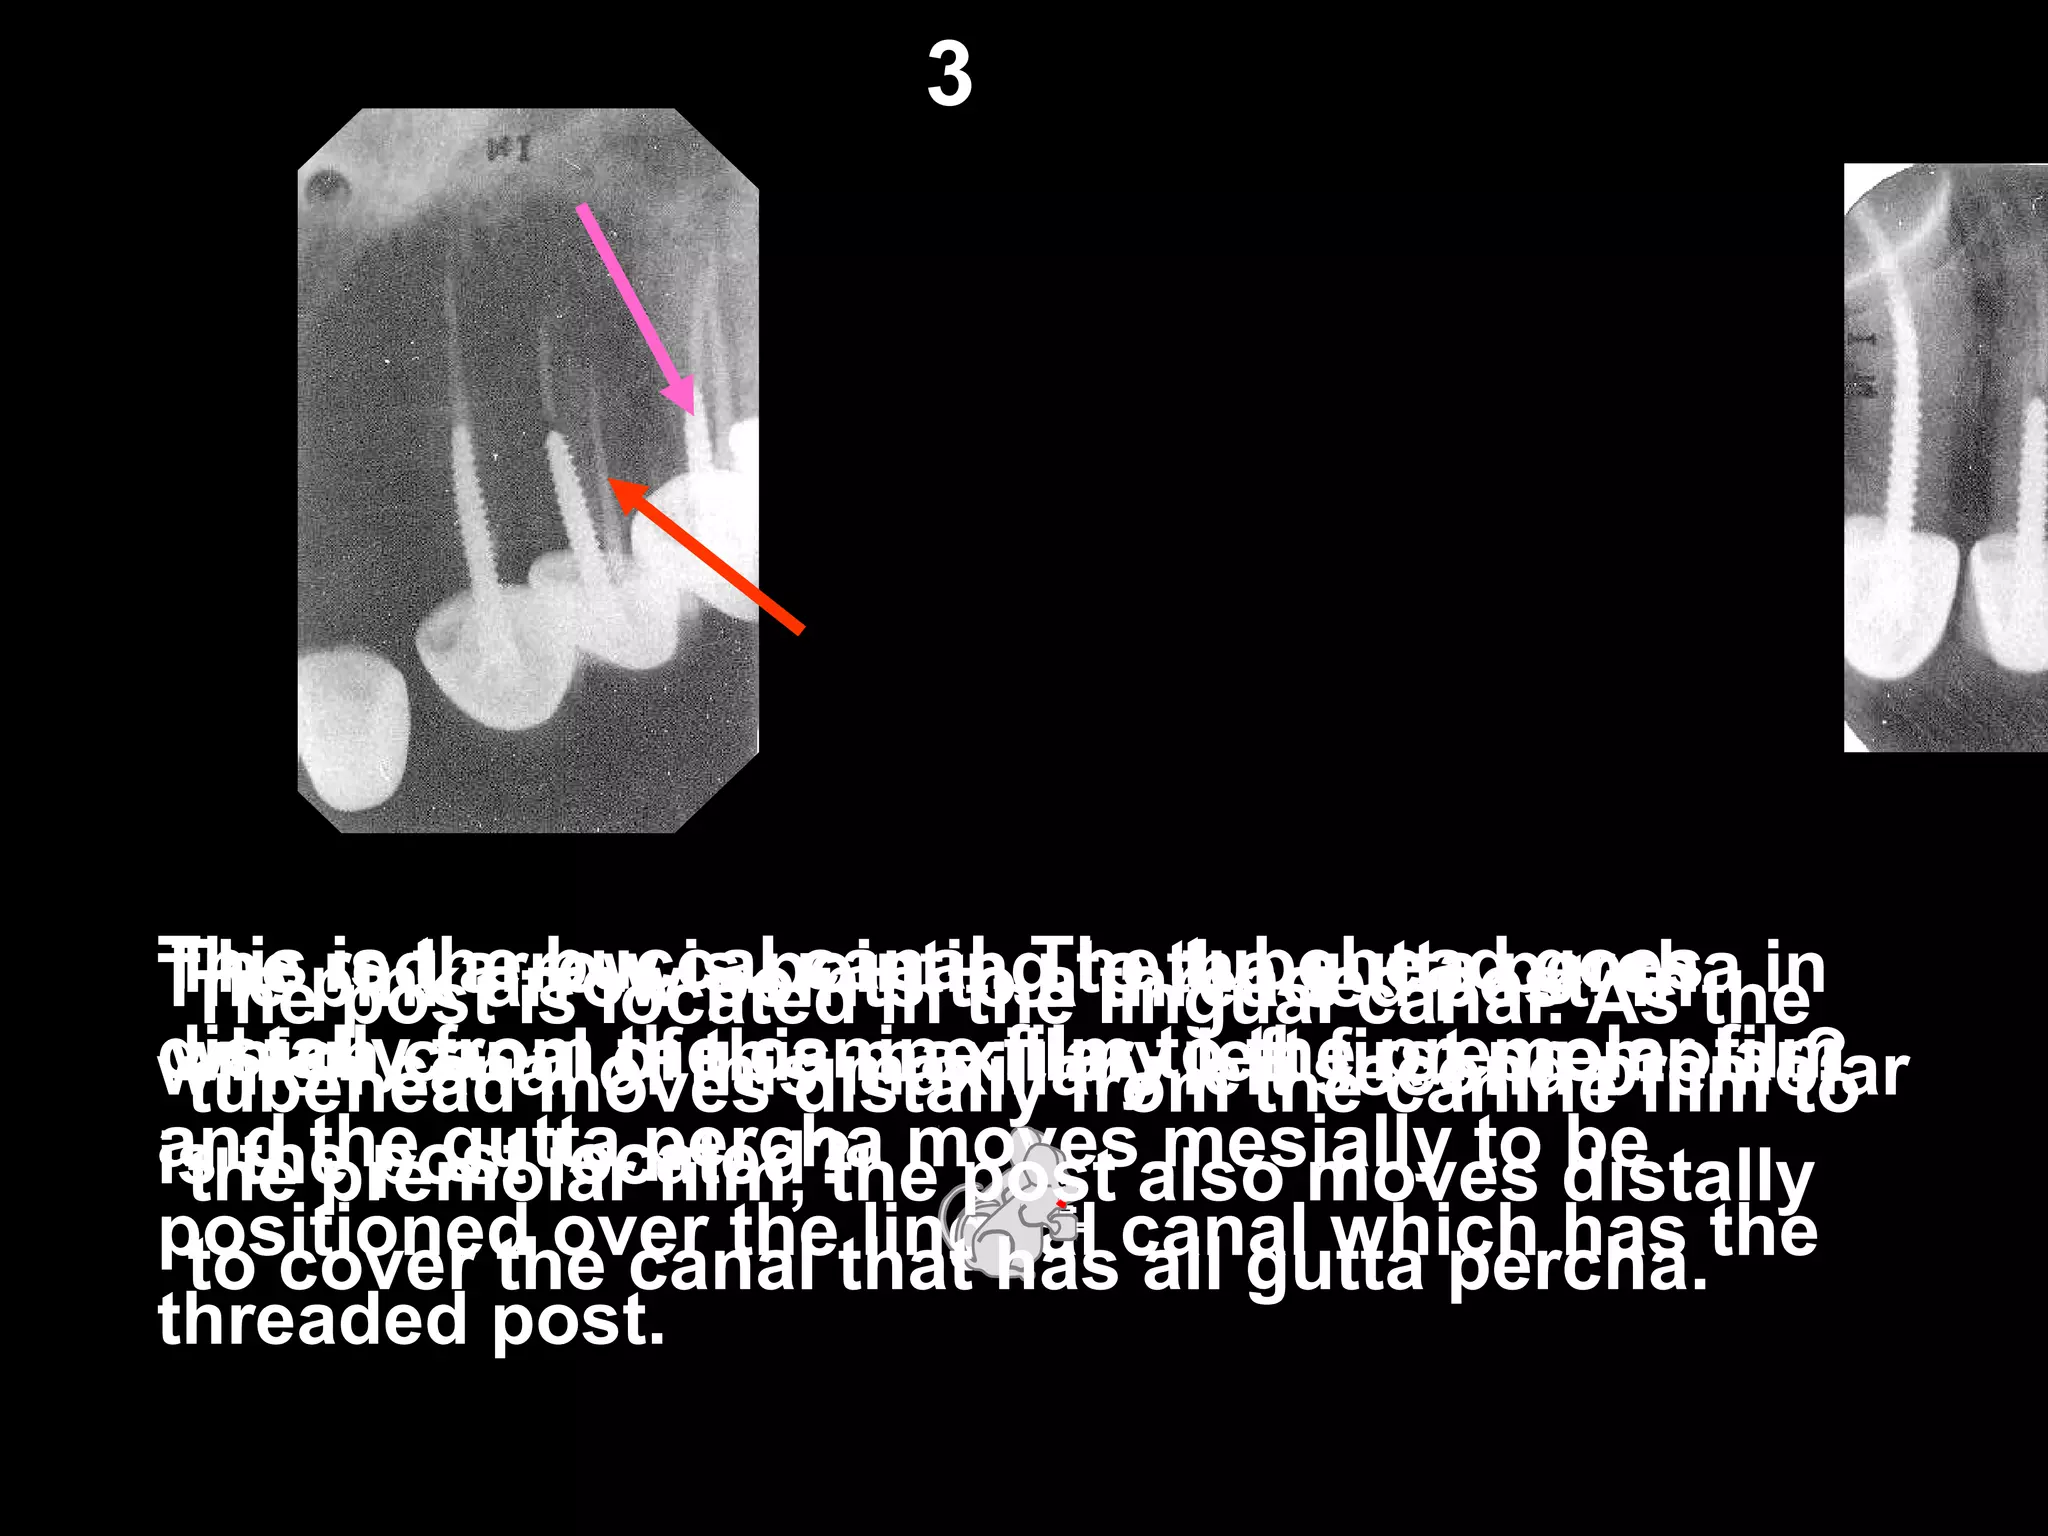

The red arrow is pointing to the gutta percha in

which canal of this maxillary left first premolar?

This is the buccal canal. The tubehead goes

distally from the canine film to the premolar film

and the gutta percha moves mesially to be

positioned over the lingual canal which has the

threaded post.

The pink arrow points to a threaded post. In

which canal of this maxillary left second premolar

is the post located?

The post is located in the lingual canal. As the

tubehead moves distally from the canine film to

the premolar film, the post also moves distally

to cover the canal that has all gutta percha.

3